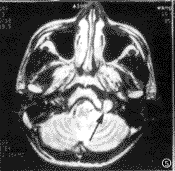

图4 右侧颈静脉-鼓室球瘤,增强后横轴位T1WI示右侧鼓室内小病灶明显强化(白箭),其外方乳突积液无强化(箭头)